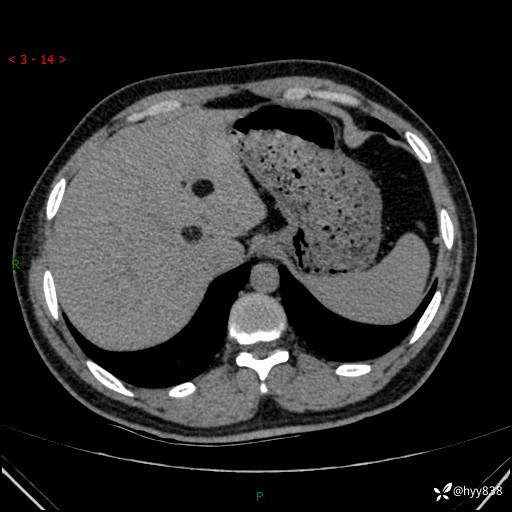

患者性别:男

患者年龄:28岁

简要病史:右肾肿瘤术后,常规复查

辅助检查:CT

临床诊断:右肾肿瘤术后

讨论:病变性质?

腹部CT+颅脑CT平扫